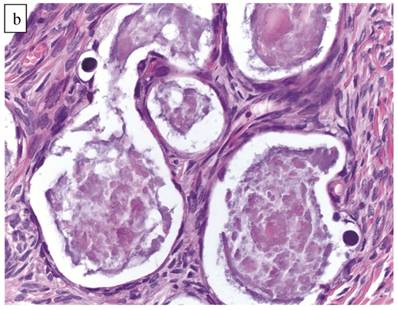

The clinicopathologic features with respect to age, stage, bilaterality, tumor size, gross appearance, and distributions of grade and architectural pattern are shown in Table 4. The histologic appearance was similar to that of the CA components of CA(AF+). Complex intra-cystic growth without destructive invasion of underlying normal ovarian stroma was common (Fig. 5). Twenty-nine tumors (10%) had a mixed carcinoma component of non-clear cell type, 9 of which were associated with endometriosis. A comparison with adenofibromatous clear cell CAs is shown in Table 4.

Figure 5

Clear cell carcinoma arising within an endometriotic cyst. The tumor is entirely intra-cystic.

Associations with endometriosis, including comparison with adenofibromatous clear cell CAs, are shown in Tables 2, 3, and 5. The 57 CAs with endometriosis in the ovarian tumor had the following histologic patterns: tubulocystic (n=4), glandular (n=1), solid (n=4), and papillary (n=8). Mixed patterns occurred in 40. Thirty-one of the 46 (67%) cases arising directly within an endometriotic cyst had a predominantly cystic gross appearance. Foci of epithelial atypia in endometriosis in the ovarian tumor were similar to those in endometriosis associated with APTs noted above (Figs. 6 and 7).